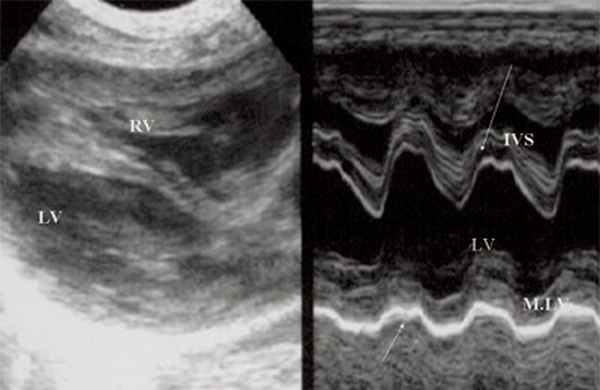

Для левого желудочка признаком объемной перегрузки являются увеличение полости левого предсердия и желудочка, а также экскурсии межжелудочковой перегородки и миокарда задней стенки левого желудочка (рис. 4).

Рис. 4. Объемная перегрузка левых отделов сердца. В- и М-сканирование. Отмечается усиление экскурсии межжелудочковой перегородки и миокарда задней стенки левого желудочка.

IVS - межжелудочковая перегородка, MLV - миокард левого желудочка, LV и RV - левый и правый желудочек.